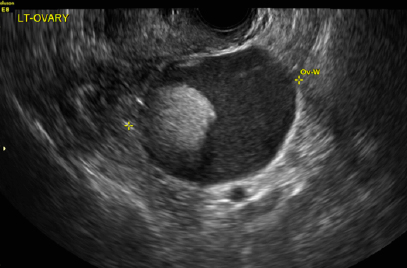

What pathology are we seeing in this image?

Gartner cyst